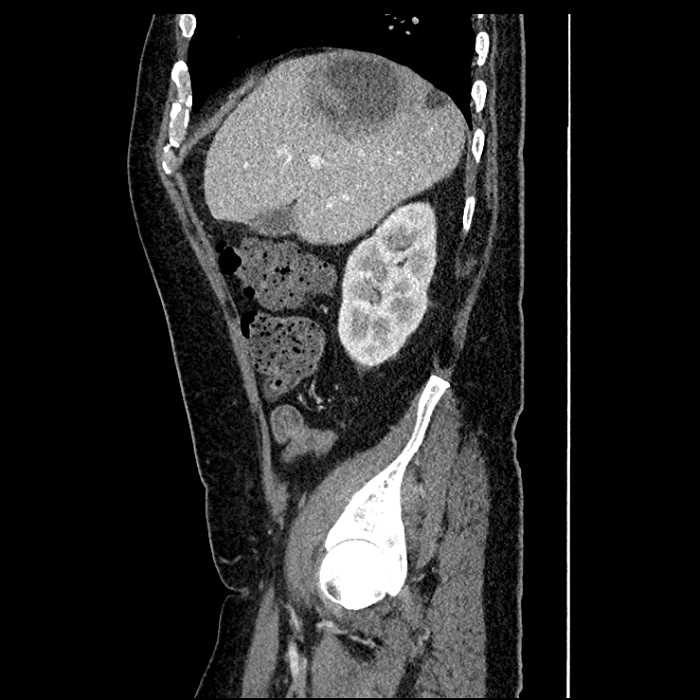

• Large fluid density structure in hepatic segments 7 and 8 measuring 10 x 7 x 7 cm with internal septation and circumferential ill-defined low density compatible with edema

• Peripherally enhancing subcapsular collections along the anterior margin of the left hepatic lobe measuring 3 x 1 cm and 2 x 1 cm

• Clearly marginated fluid density structure in segment 7 and several other scattered tiny hypodensities, which likely represent cysts

Acute sigmoid diverticulitis complicated by a small contained perforation and a large abscess in the right hepatic lobe. Additional small subcapsular abscesses along the anterior margin of the left hepatic lobe.

• The classic CT imaging appearance is a double target sign with internal low density surrounded by an internal enhancing rim (capsule) and a low density external rim (edema)

Hepatic abscess showing the double target sign with low density internally surrounded by a thin inner enhancing rim (red arrow) and ill-defined outer low density rim (yellow arrow). Blue arrow indicates an internal septation. Red arrows: additional smaller subcapsular abscesses. Red arrow: focal contained perforation associated with diverticulitis.